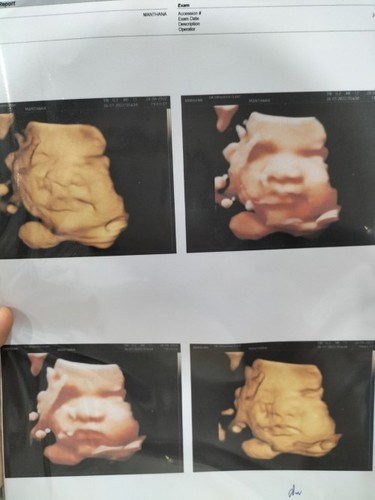

บ้านนี้35+2 น้ำหนัก3+++แล้วคับ แม่ต้องฉีดยาทุกอาทิตย์เลย เพราะแม่มีอาการท้องปั้น+หน่วงท้อง (เด็กน้อยอารมณ์ดีมีแอบยิ้มมุมปาก☺️🤣)